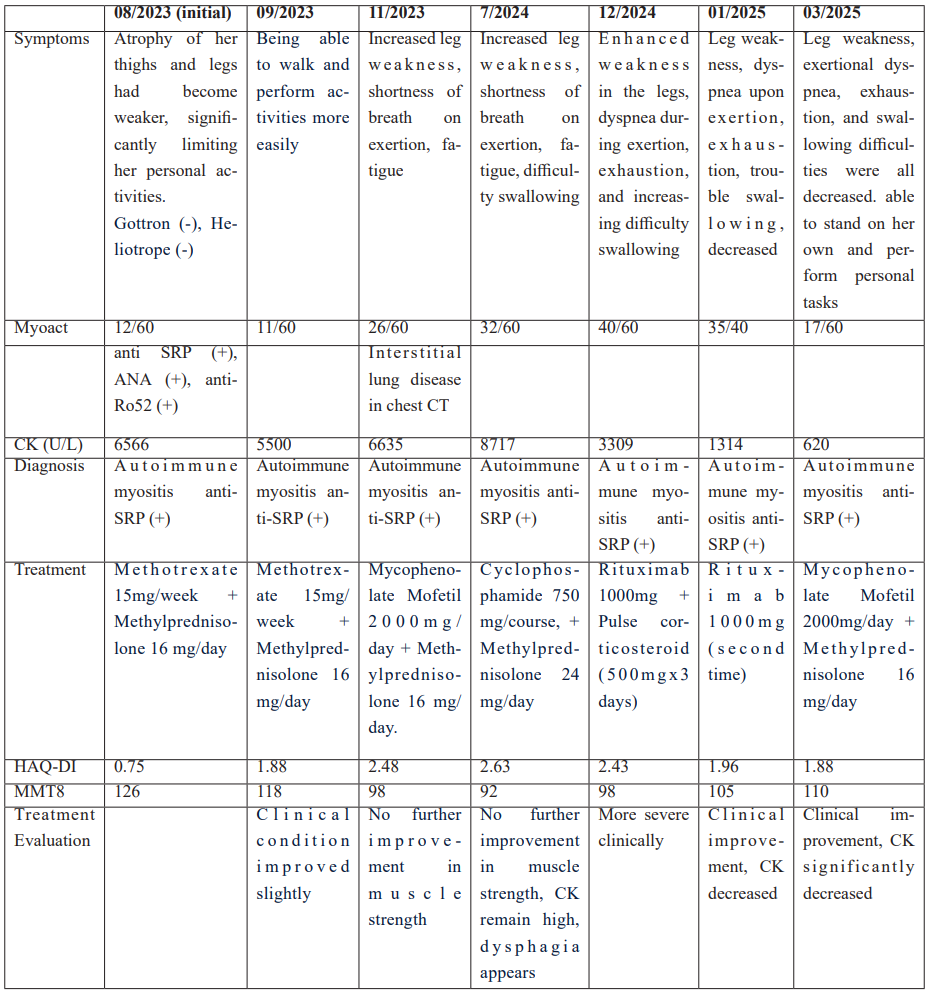

A 55-year-old female with no significant medical history and no previous internal or autoimmune diseases was examined at the Musculoskeleton Clinic due to progressive leg weakness over the last 3 years. In March 2022, she started experiencing fatigue and mild weakness along with numbness in both legs, without any lower back pain, and was still able to work and perform her usual activities. She visited the clinic and was diagnosed with uterine fibroids that were compressing the nerve and muscle, leading to her undergoing a hysterectomy. Nevertheless, she continued to have leg weakness after the surgery. When the patient arrived at the musculoskeletal clinic, she had to place both hands on the floor in order to stand up because of weakness in both lower limbs (Figure 1). The progression of the patient's illness is as follows in Table 1.

Table 1: The progression of the patient's illness (symptoms, laboratory, diagnosis and treatment) in 2 years.

Figure 1: The patient had weak muscles in the limbs, difficulty standing up, and need to place both hands on the ground to stand.